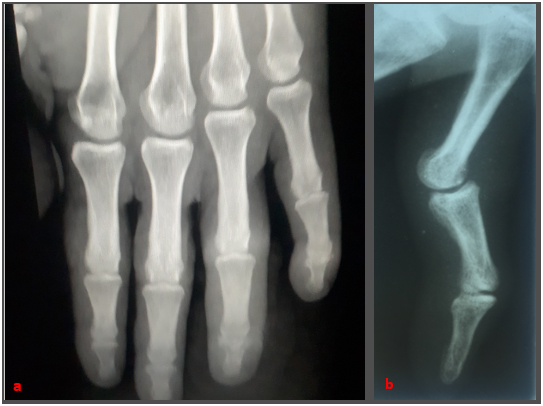

In the patient's final evaluation six months after the procedure, the flexion range of the metacarpophalangeal, proximal and distal interphalangeal joints of the injured finger was 90°, 90° and 70°, respectively. The total active movement of the injured finger was 160°, which is excellent for the Strickland and Glogovac criteria4 (Figure 5).

Figure 5a,b Control X-ray at six months of evolution confirms fragment consolidation with good articular congruence.